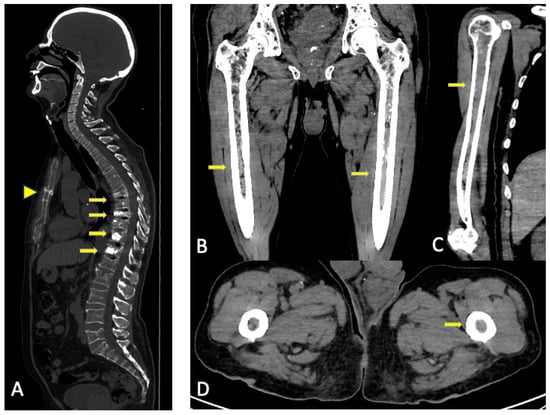

9. Complications

3.5. Limitations

3.2. Imaging Findings